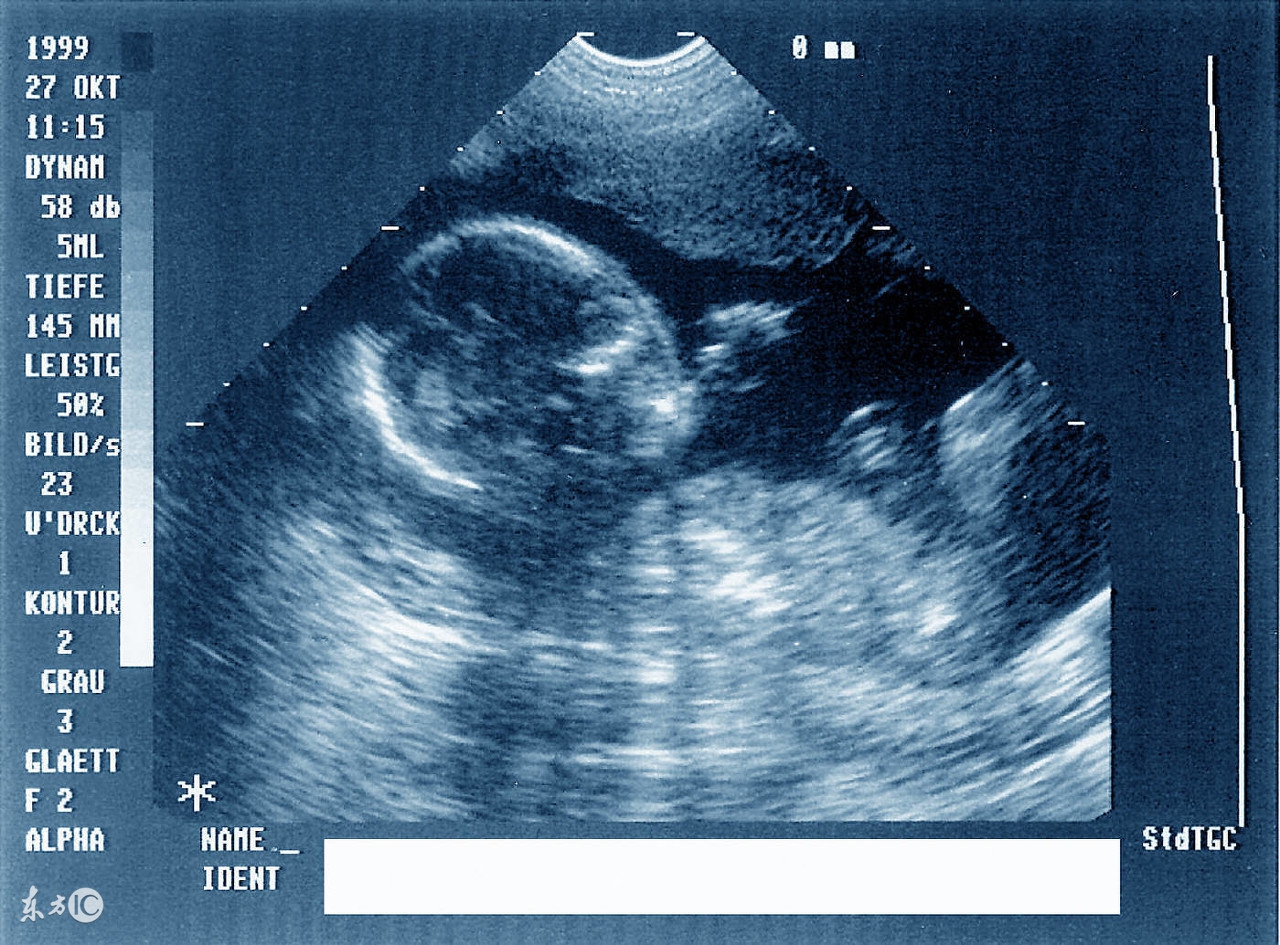

2、妊娠中晚期,了解胎儿生长发育的情况,以及是不是有胎儿宫内发育的迟缓。胎儿发育到35周(8-9个月时)左右,血管系统已经成形,这时做彩色超声波检查,就可以清晰了解孩子的心脏、脑部、肾脏等重要器官血流情况,如果有严重疾病或者其他病变,能够及时采取合理措施。